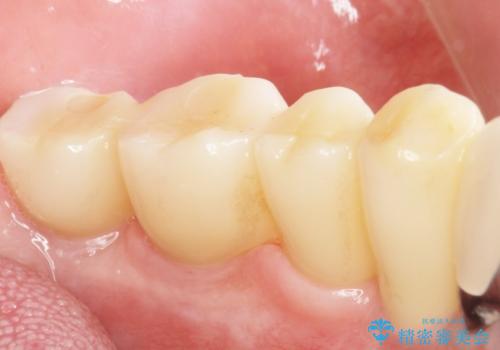

奥歯で咬むことができるようになり、喜んで頂けました。

治療終了後には「なんでも食べられるようにしてくれてありがとうございます!」とおっしゃって下さいました。

インプラントの種類:スプラインツイスト(HAコーティング)

固定様式:スクリュー固定

クラウンの種類:ベレッツァクラウン